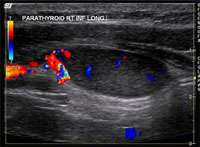

Major advances in surgical technique, particularly the advent of focused (minimally invasive) parathyroid surgery, have made parathyroid surgery a better option for increasing numbers of people worldwide

(Figure 8).

Growing awareness of the health benefits of parathyroid surgery has also driven this trend, which reflects a general shift in the risk-benefit ratio in favor of surgery.

Figure 8. Worldwide trends in parathyroid surgery. Members of the International Association of Endocrine Surgeons have reported increasing rates of parathyroid surgery across all continents. (Adapted from Sackett, Arch Surg 2002)